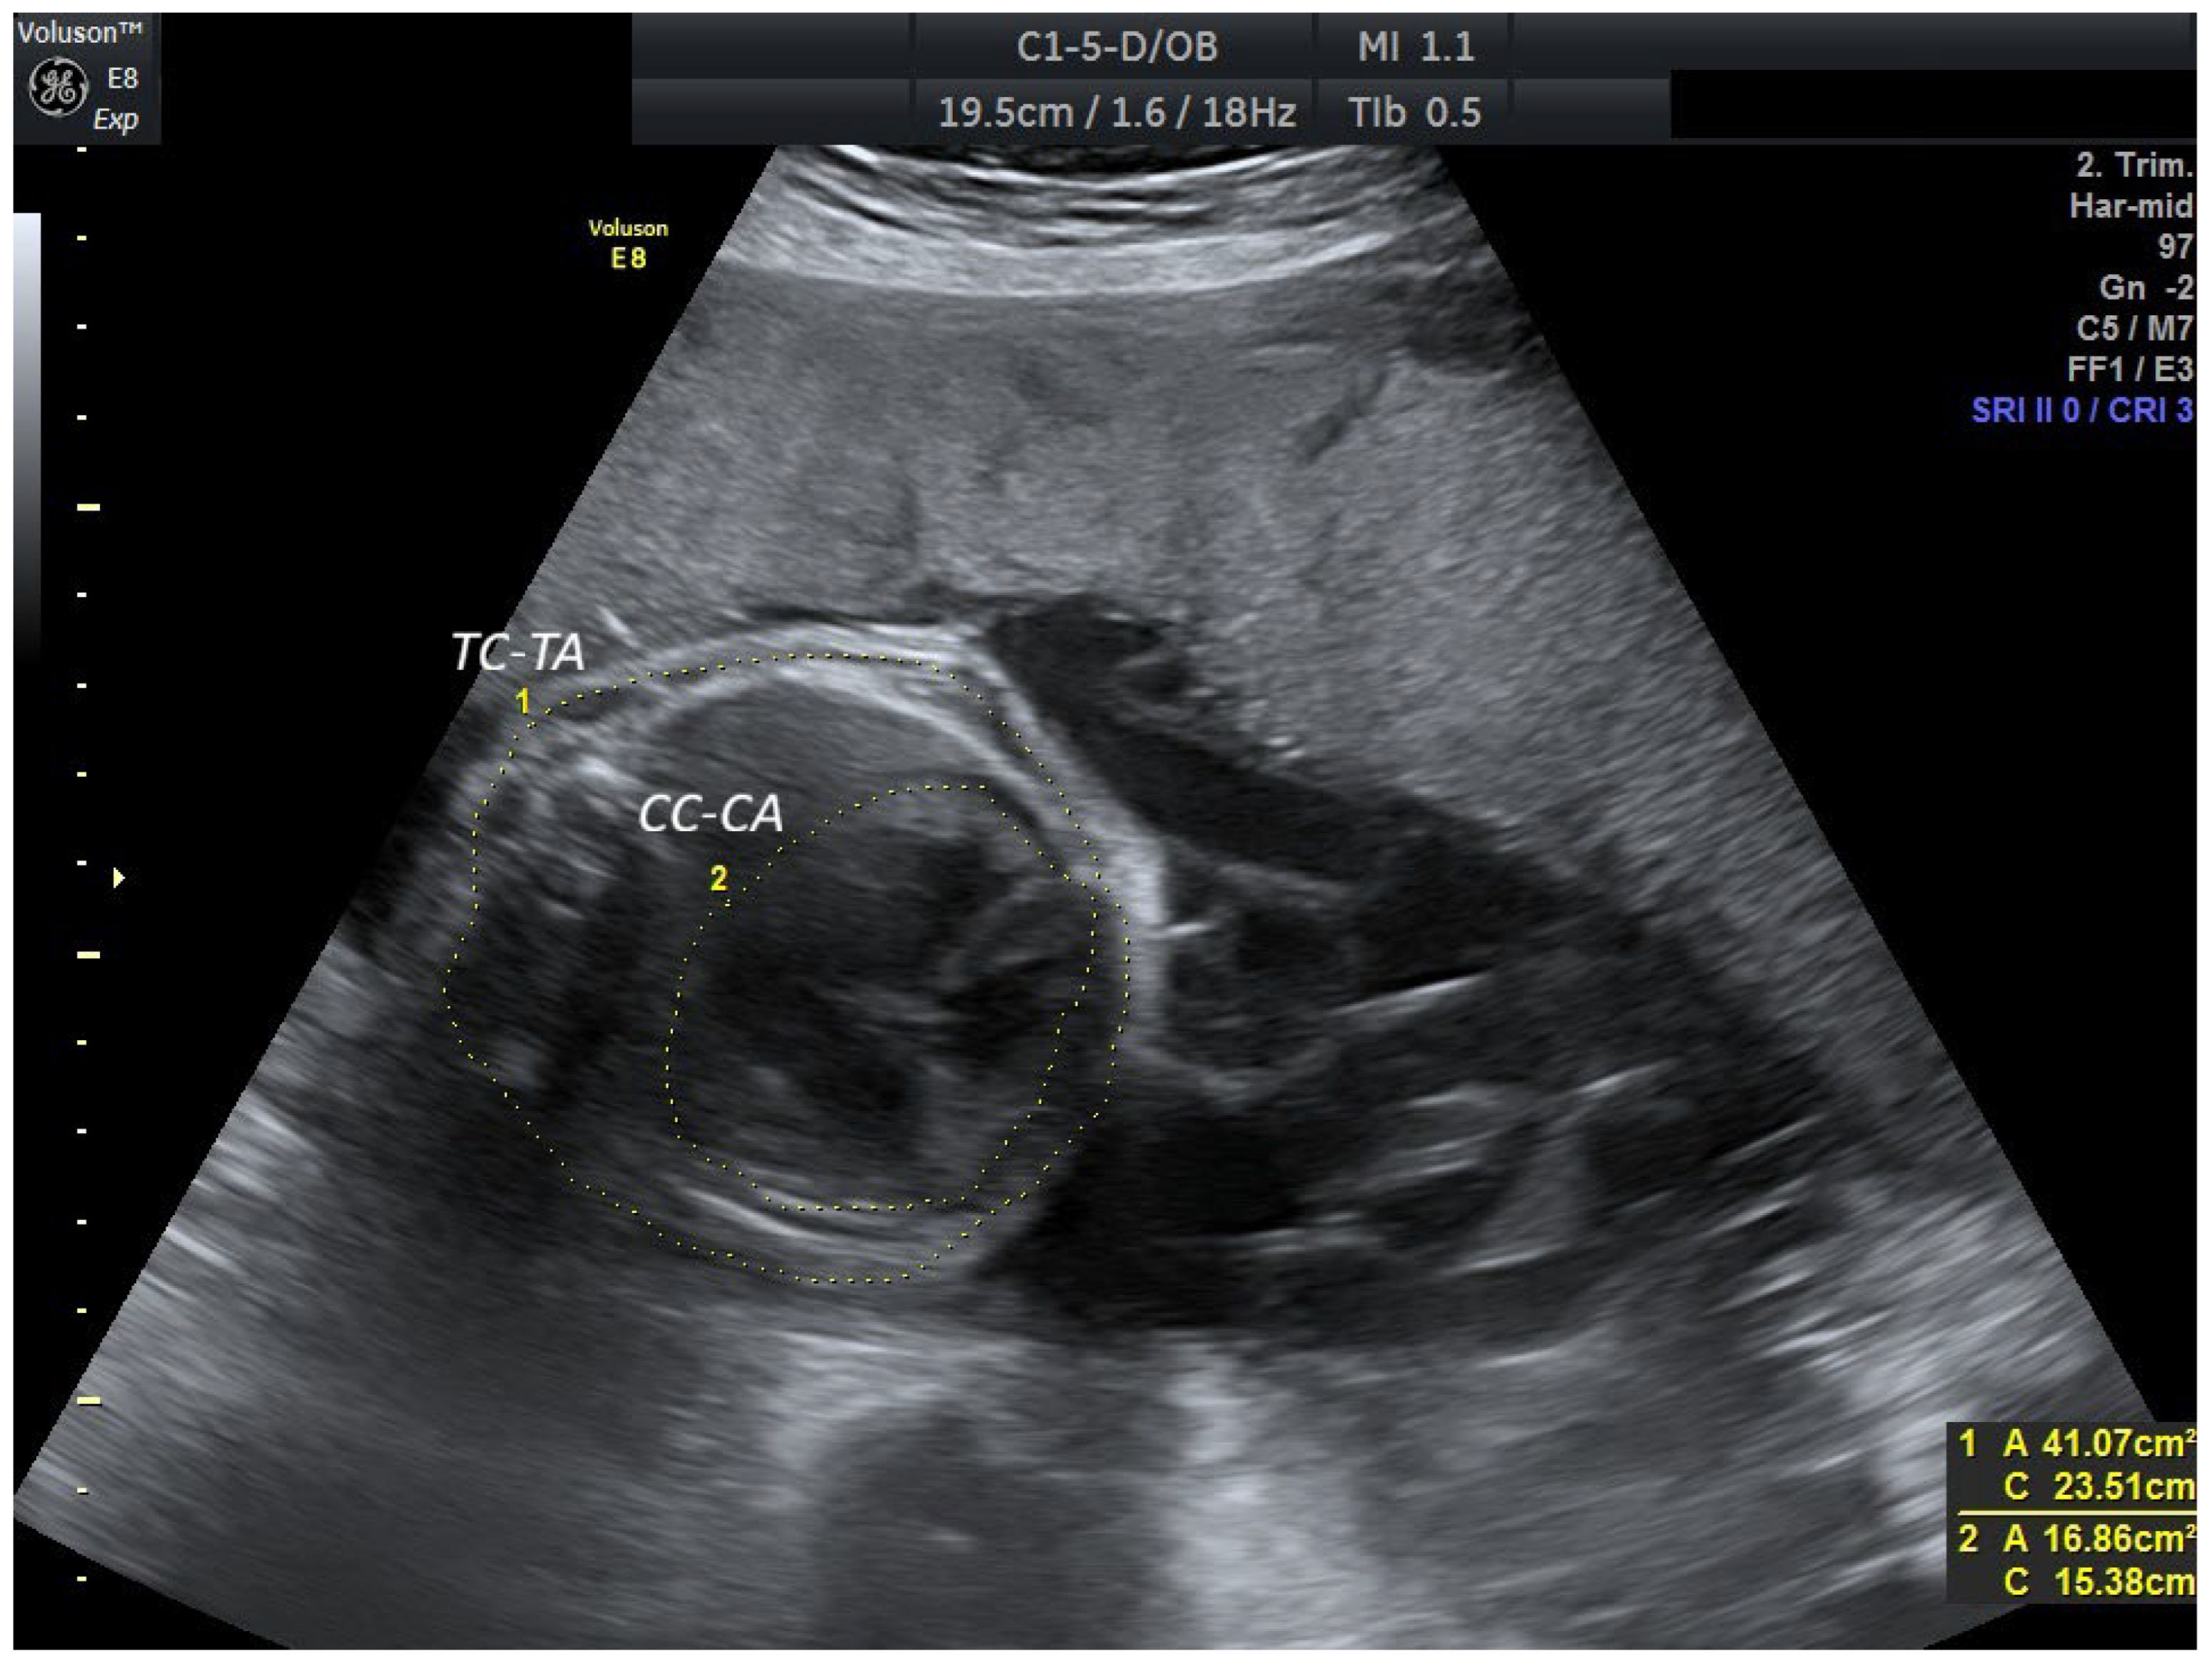

2. Case Report